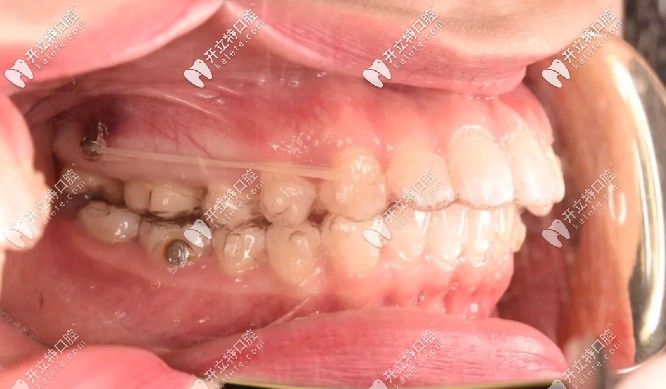

為了不拔牙,在設(shè)計(jì)方面時(shí)就溝通了打骨釘,我是在第18副的時(shí)候打的骨釘,看圖▼